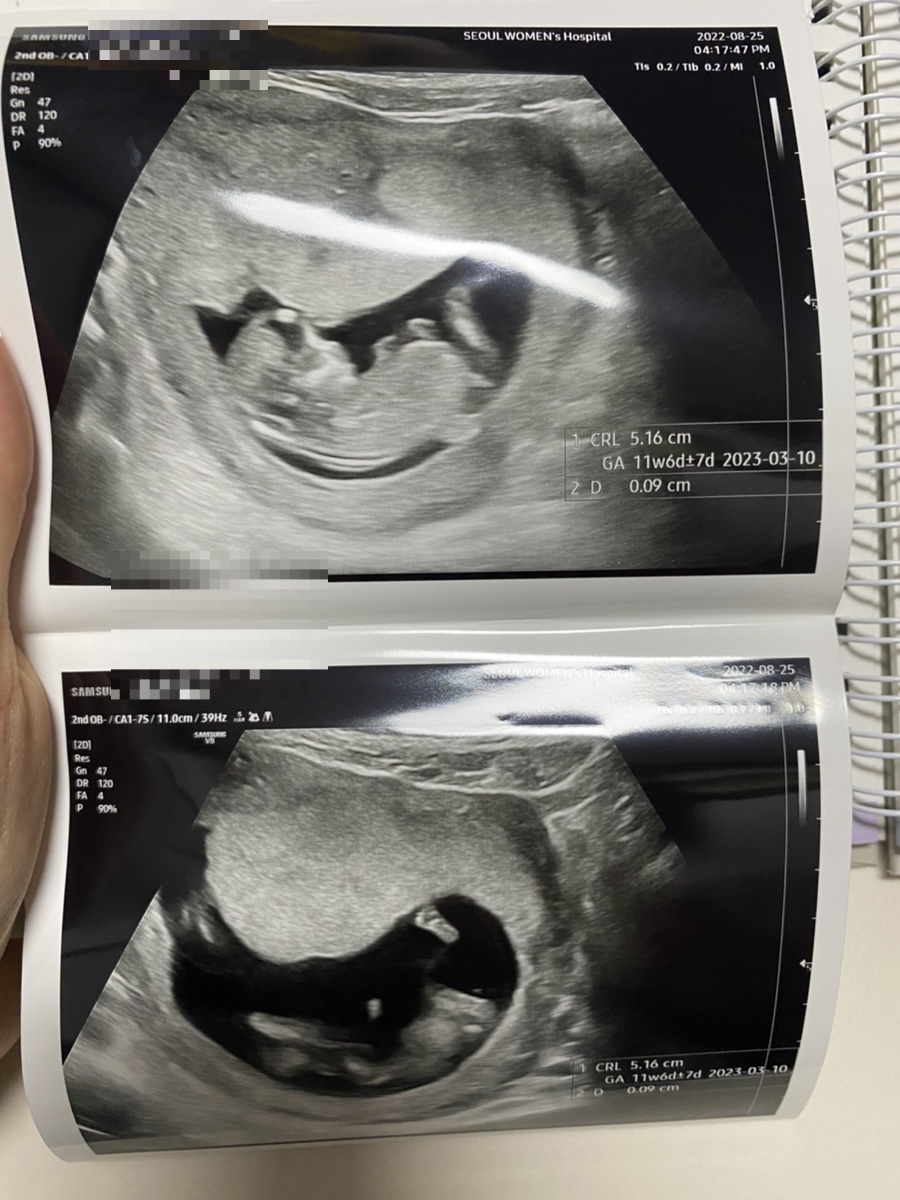

오랜만에 만난 장식은 커지고 있었다.이제 제법 얼굴 팔 다리 손 다리가 있다.

엉덩이로 점프도 하고

초음파를 보다가 나를 놀라게 한 이 사진! 설마 이거 고추예요?

의사 선생님께서 11주에는 음경인지 음핵인지 모른다고 하셨다. 여자 아이든 남자 아이든 다 뛰쳐나오고 16주가 되면 여자 아이는 들어오고 남자 아이는 더 튀어나오니까 그때 정확하게 성별을 알려준다고 했다.